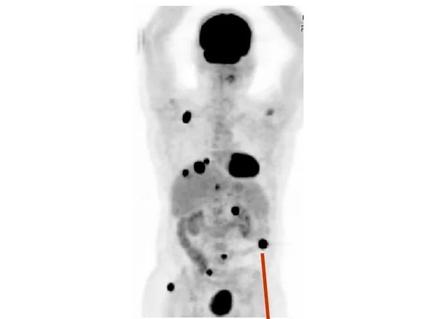

Doctors have known for decades that melanoma and many other cancer types tend to spread first into nearby lymph nodes before entering the blood and traveling to distant parts of the body. But the implications of this detour through the lymph nodes have remained unclear.

The study, published September 3 in Nature, shows that melanoma cells that pass through the lymphatic system before entering the bloodstream spread and form new tumors more readily than cells that directly enter the bloodstream.

Dr. Morrison’s team found that human melanoma cells injected into lymph nodes in the mice were more likely to form distant tumors than melanoma cells injected into blood.

As added support of lymph’s protective effects, the team found that when they collected melanoma cells from lymph nodes and from a primary tumor beneath the skin of one mouse and injected them into the blood of other mice, the lymph-dwelling cells were better able to survive and form metastatic tumors than those from the primary tumor.